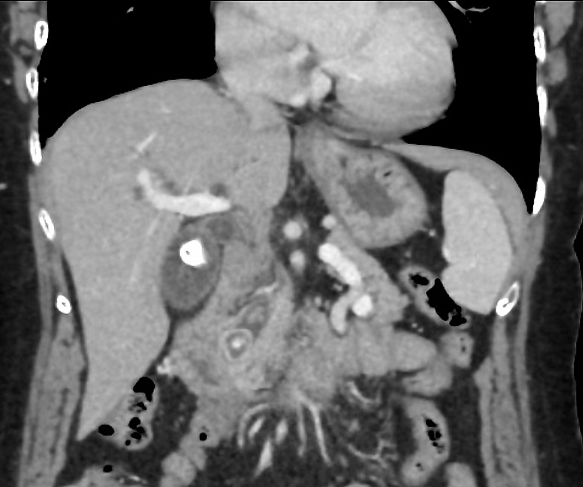

Images hyperdense multiple de calcul

vesicule biliaire , Coupe TDM

frontal (coronal ) de contrast intraveineuse . |

Meme cas en coupe

axial . Les calculs sont multiple a hyperdense dans

la vesicule hypodense que le foie |